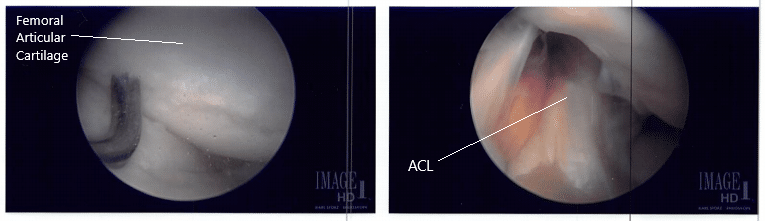

The scope was entered into the patellofemoral joint, where there was grade III to grade IV arthritis and over the trochlea, grade I to grade II over the posterior surface of the patella. Shaver and punch were used to remove all the loose cartilage from the trochlea as well as the patella. The cartilage was balanced to a stable margin. The knee was again examined and found to be adequately debrided.

Intraoperative arthroscope images.